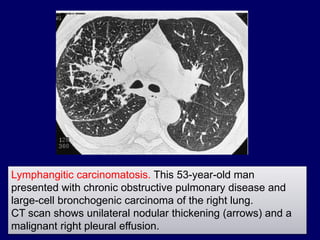

Lymphangitic carcinomatosis. This 53-year-old man

presented with chronic obstructive pulmonary disease and

large-cell bronchogenic carcinoma of the right lung.

CT scan shows unilateral nodular thickening (arrows) and a

malignant right pleural effusion.

Lymphangitic carcinomatosis. This53-year-old man presented with chronic obstructive pulmonary disease and large-cell bronchogenic carcinoma of the right lung. CT scan shows unilateral nodular thickening (arrows) and a malignant right pleural effusion.